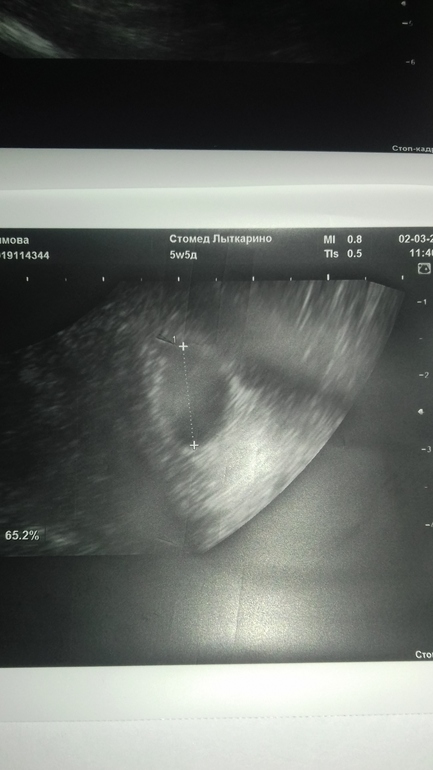

УЗИ, КТГ, доплерДевочки, кто опытный, успокойте и оцените. Сегодня в 3+5 эмбрионального и 5+5 акушерского сходила на первое узи. ПЯ в матке размером 12.2 на 11.3 мм, ЖМ 2.02 мм (На фото снизу). Это ок для такого срока?

А еще огромная киста в правом яичнике, тянет этот бок - зараза.. Величиной 5х4 см (на фото сверху). Хотя Ре сказала, что это может быть ЖТ! Что теперь будет, если это киста? У кого было такое?